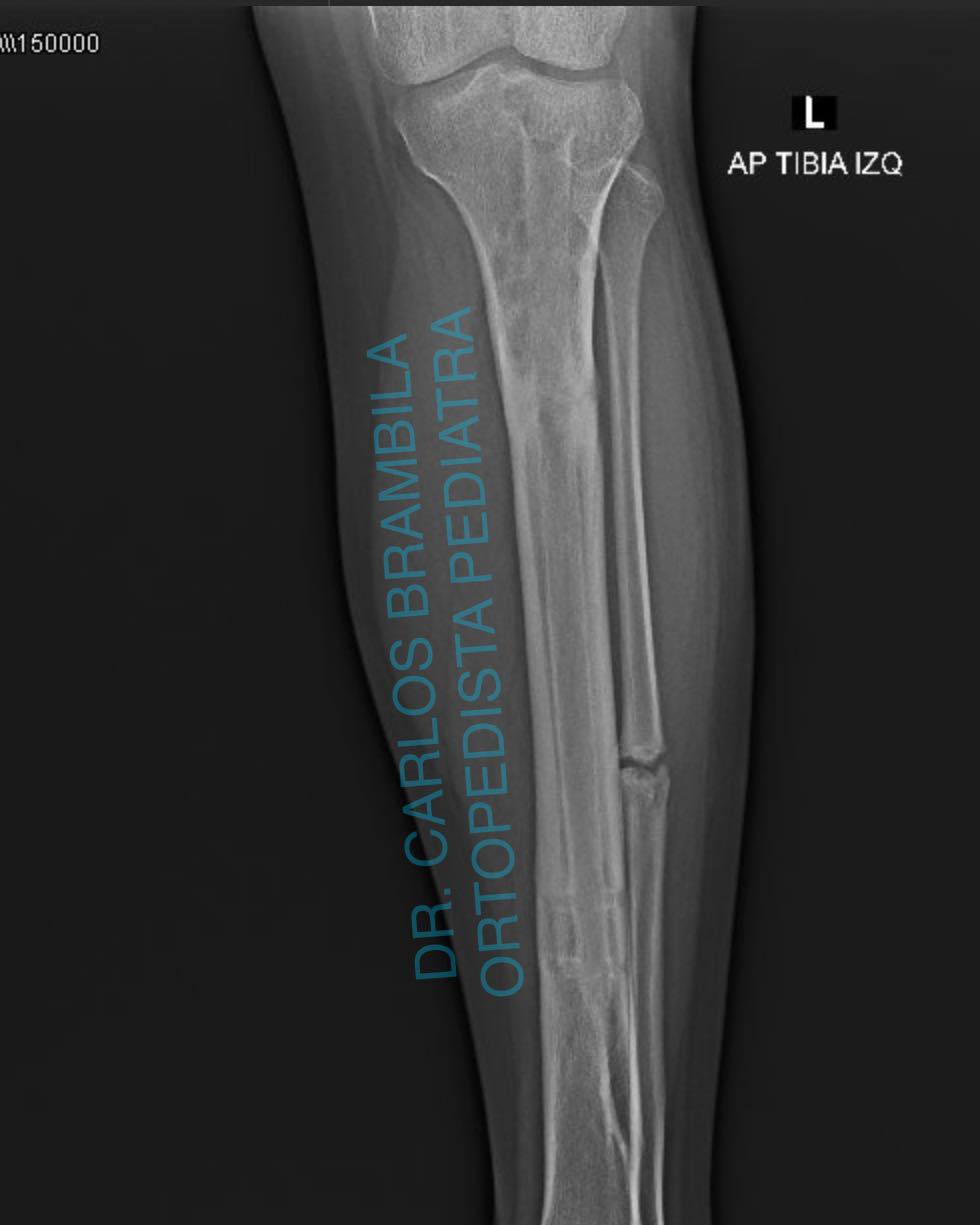

Hoy es un día especial y quiero aprovechar para compartir el caso de Emiliano, un joven de 17 años originario de Nayarit. Emiliano acudió conmigo por una deformidad en su pie, la cual había sido tratada quirúrgicamente en varias ocasiones sin éxito. Iniciamos un tratamiento con yesos, seguido de una cirugía para el balance neurológico del pie. Ahora, después de 5 meses, este es el resultado: Emiliano ya no necesita bastón para caminar y puede vivir libre y feliz.